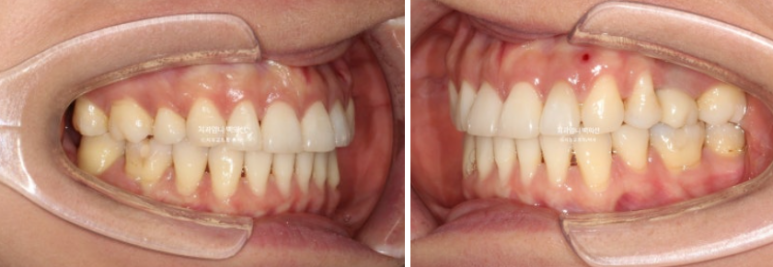

23.08~25.06

파란 화살표 임플란트가 들어가며 좌우 치아갯수가 맞아졌습니다.

덕분에 중심선도 개선하고 어금니 교합관계도 1급이 되었으며 앞니가 뒤로 쓰러진 옥니도 고칠 수 있었습니다.

소량의 치간삭제로 기존의 블랙트라이앵글 사이즈를 줄였습니다.